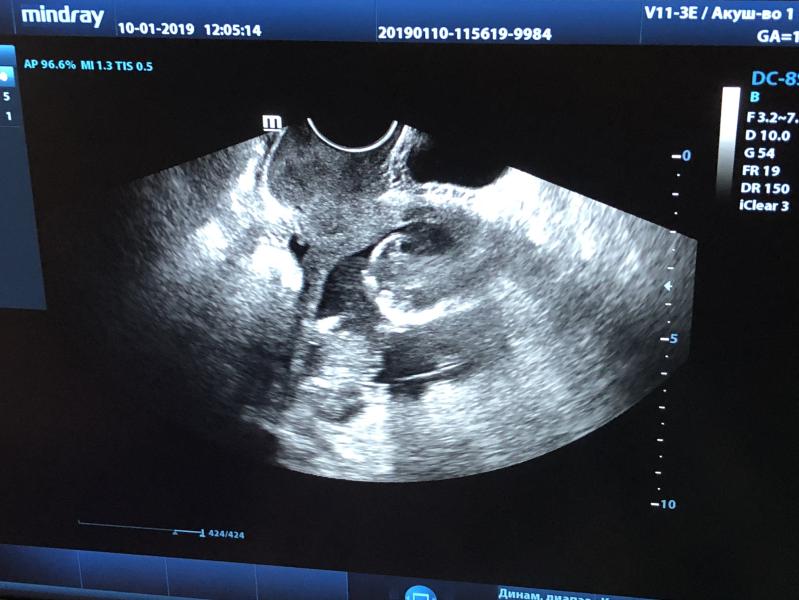

Не думала я, что на 14 недели узи первого триместра мне будут делать вагинально 😲 А все потому, что врач заболел, а там где принимаем зав отделением гинекологии слабый датчик 🙈 Однозначно, второй и третий скрининг пойду делать платно 😊Пол пока не сказали, но малышок сидит на попе 😅, показывает кулак и гладит голову. Такой он хорошенький

У меня в 12 недель ребенок неудобно лежал для замеров, пришлось вагинально, платно делала в 1- недель, и так, и так смотрели

Мне перед скринингом с датчика всё увидели, на 9-10 недели, а вагинально ничего не было видно, так как датчик там у них слабый. Всё от оборудования зависит

Я на учете платно в клинике стою и все два пока узи делали и так и так, и датчики там хорошие, просто четко сверху шейку не измерить, а данные нужны более четкие, потому что 1-3 мм будут иметь смысл